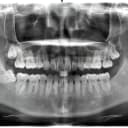

OPG (عکس کامل فک)